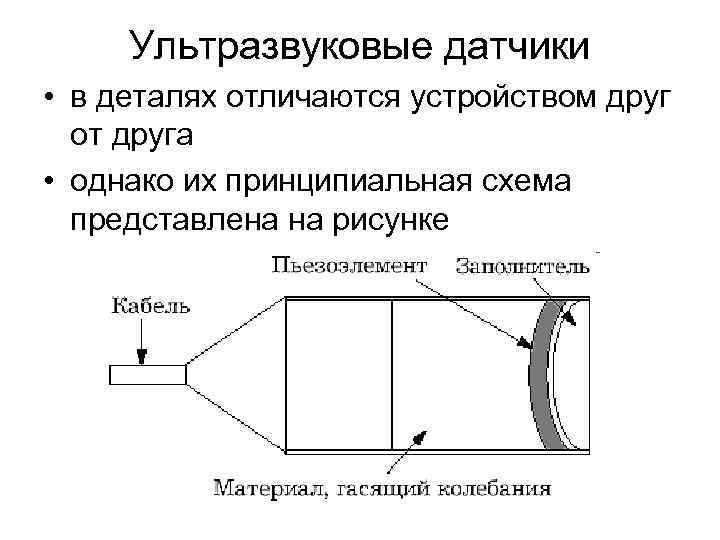

Ультразвуковые датчики • в деталях отличаются устройством друг от друга • однако их принципиальная схема представлена на рисунке

Ультразвуковые датчики • в деталях отличаются устройством друг от друга • однако их принципиальная схема представлена на рисунке